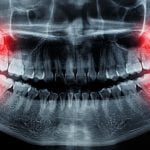

رادیوگرافی

رادیوگرافی دندانها میتواند به دندانپزشک کمک کند تا میزان تخریب استخوان و بافتهای حمایتی دندان را ارزیابی کند. این تصاویر همچنین میتوانند وجود تارتار و پاکتهای پریودنتال را نشان دهند.